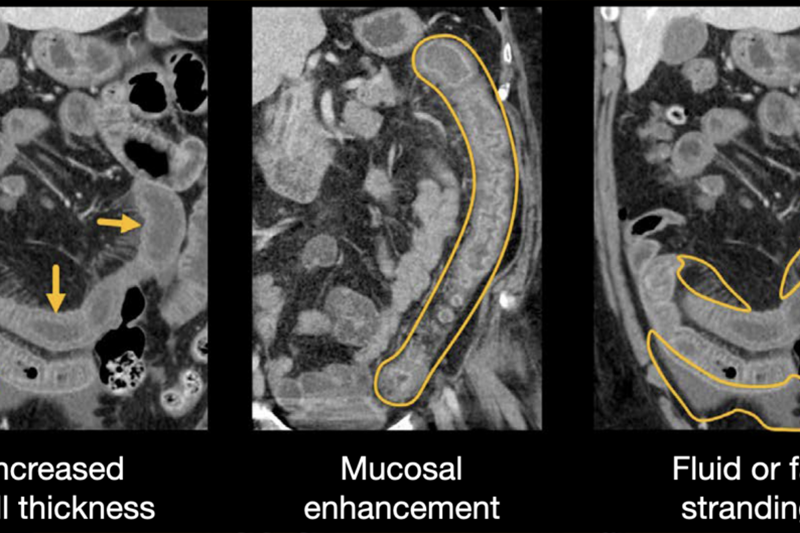

Nghiên cứu hình ảnh bằng chụp cắt lớp vi tính (CT) đa dãy và có thuốc cản quang ổ bụng đã xác định được các dấu hiệu đặc trưng có thể phân biệt viêm đại tràng nhiễm khuẩn với các loại viêm đại tràng không nhiễm khuẩn, bao gồm bệnh viêm ruột (IBD). Khi các đánh giá lâm sàng và xét nghiệm phân ban đầu không chẩn đoán được tác nhân gây bệnh đường ruột, viêm đại tràng dai dẳng hoặc tái phát, hoặc nghi ngờ viêm đại tràng do C. difficile, CMV hoặc trung gian ức chế điểm kiểm soát miễn dịch, nội soi đại tràng hoặc nội soi đại tràng sigma mềm kèm theo sinh thiết niêm mạc được khuyến nghị để chẩn đoán. Ở những bệnh nhân có tiền sử quan hệ tình dục qua đường hậu môn, nên xem xét viêm trực tràng do các bệnh lây truyền qua đường tình dục (lậu, chlamydia, giang mai, herpes simplex virus) trong chẩn đoán, được đánh giá bằng soi hậu môn, phết trực tràng và các xét nghiệm trong phòng thí nghiệm (nuôi cấy, PCR hoặc soi trực tiếp).

Hình ảnh CT viêm đại tràng